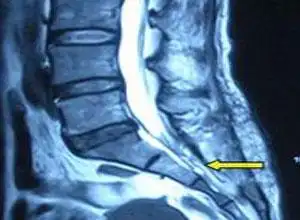

女性腰椎间盘突出图片(腰臀或下肢痛) - 赤虎壹号

病例:这才24岁,怎么就患上腰椎间盘突出症呢?_霍同学